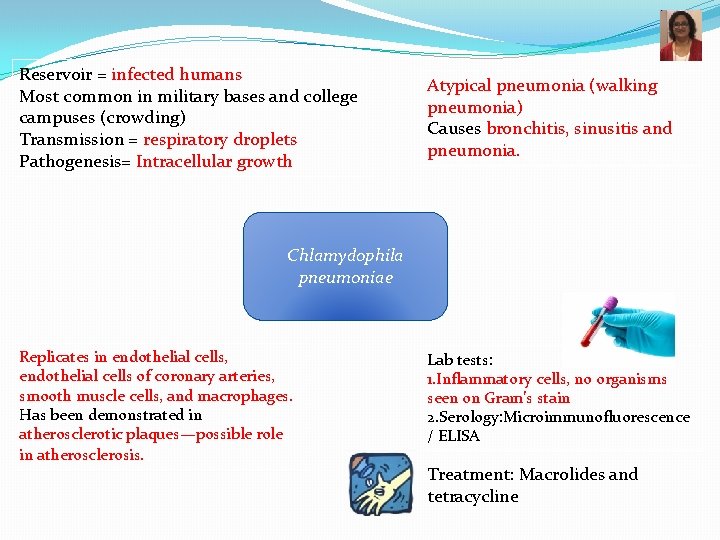

Reservoir = infected humans Most common in military bases and college campuses (crowding) Transmission = respiratory droplets Pathogenesis= Intracellular growth Atypical pneumonia (walking pneumonia) Causes bronchitis, sinusitis and pneumonia. Chlamydophila pneumoniae Replicates in endothelial cells, endothelial cells of coronary arteries, smooth muscle cells, and macrophages. Has been demonstrated in atherosclerotic plaques—possible role in atherosclerosis. Lab tests: 1. Inflammatory cells, no organisms seen on Gram’s stain 2. Serology: Microimmunofluorescence / ELISA Treatment: Macrolides and tetracycline